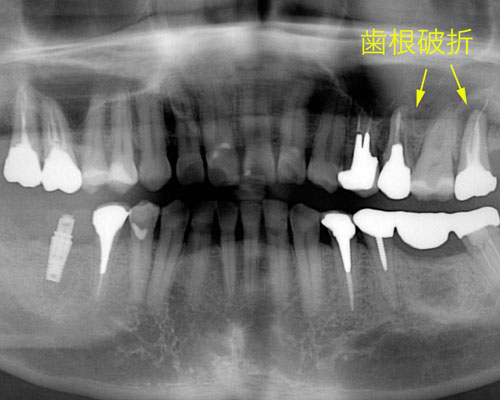

ブリッジの作り直しは無理だったため、インプラントに替えました。左上の奥のインプラントは仮歯まで漕ぎ着けています。そして5本目のインプラントを入れています。ところが、またしても右下が割れました。もう、患者さんは悲鳴をあげています。

そして、とうとう右下の3番目にインプラントを入れご覧のような状態に落ち着きました。しかし、私の診断では左側の上下2本に破折のリスクがあると説明していました。するとすぐに左下の奥から4番目が一部破折を認め作り直しとなりました。